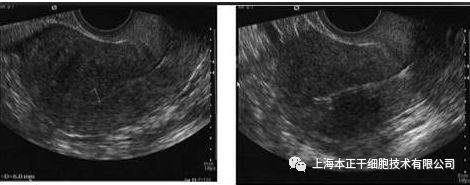

2014年,印度新德里全印度医学院妇产科和干细胞研究所的Singh博士对一位重度IUA病人进行了自体骨髓间充质干细胞治疗,病人治疗前均有继发性闭经或不孕病史,且行传统宫腔粘连分解术及雌激素治疗失败,间充质干细胞治疗后 3、6、9个月,所有病人内膜厚度较治疗前均有明显增加,其中5例病人恢复了闭经。

图1:患者移植前子宫内膜厚度

图2:同一患者移植后子宫内膜厚度